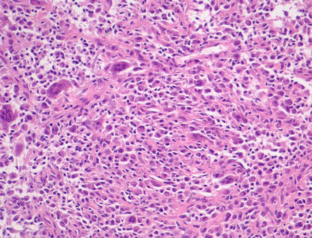

Sikaria, S., Heim-Hall, J., Diaz, E.H. et al. Partial response of a rare malignant metastatic diffuse tenosynovial giant cell tumor with benign histologic features, treated with SCH 717–454, an insulin growth factor receptor inhibitor, in combination with everolimus, an MTOR inhibitor. Targ Oncol 9, 73–79 (2014). https://doi.org/10.1007/s11523-013-0267-8